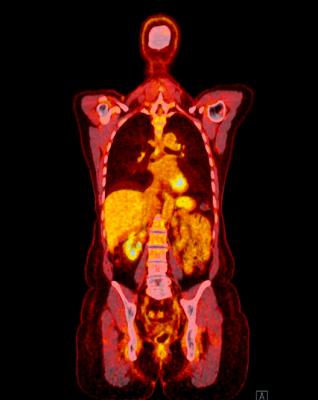

June 14, 2024 — Positron Corporation, a leading molecular imaging medical device company offering PET and PET-CT (Positron Emission Tomography/Computed Tomography) imaging systems and clinical services, announced its membership in the national alliance “Cardiac PET Industry Coalition” (CPIC), an organization at the forefront of quality of patient care, advocacy and innovation to advance the field of cardiovascular PET imaging.

The CPIC will be a leading advocate for fair and transparent coverage and reimbursement policies that facilitate access to cardiac PET, align practitioners with regard to research opportunities, highlight the clinical and economic benefit of the modality, and provide expanded opportunities to educate healthcare providers and policymakers on the overall value of cardiac PET. CPIC has begun its work by weighing in on 2024 final payment rules, engaging with stakeholders in the cardiac community, and developing a 2024 policy agenda.